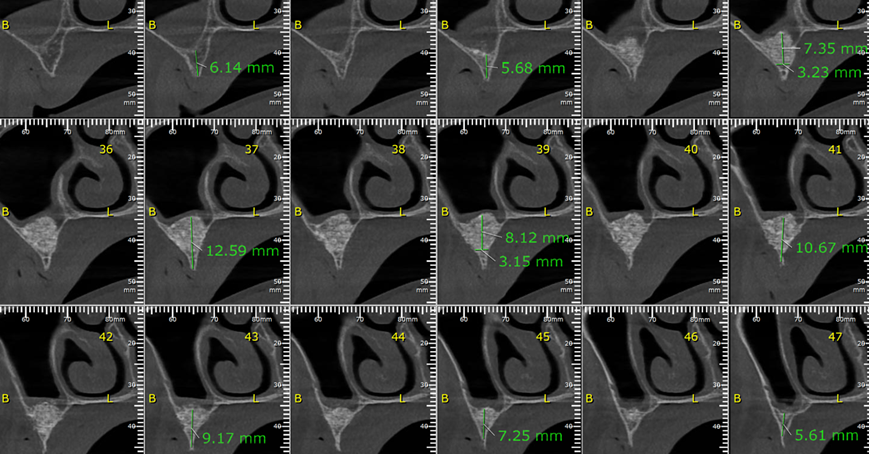

Aguardado o tempo de Osseointegração do enxerto (em torno de oito meses), solicitamos uma nova tomografia, onde foi observado ganho ósseo suficiente para a instalação de implantes, apesar de ainda ser uma condição limítrofe (Fotos 2, 3 e 4). O planejamento cirúrgico foi de instalar cinco implantes, sendo dois no lado direito e três no lado esquerdo, onde a extensão de ganho ósseo foi maior e possibilitava distribuir melhor os implantes.